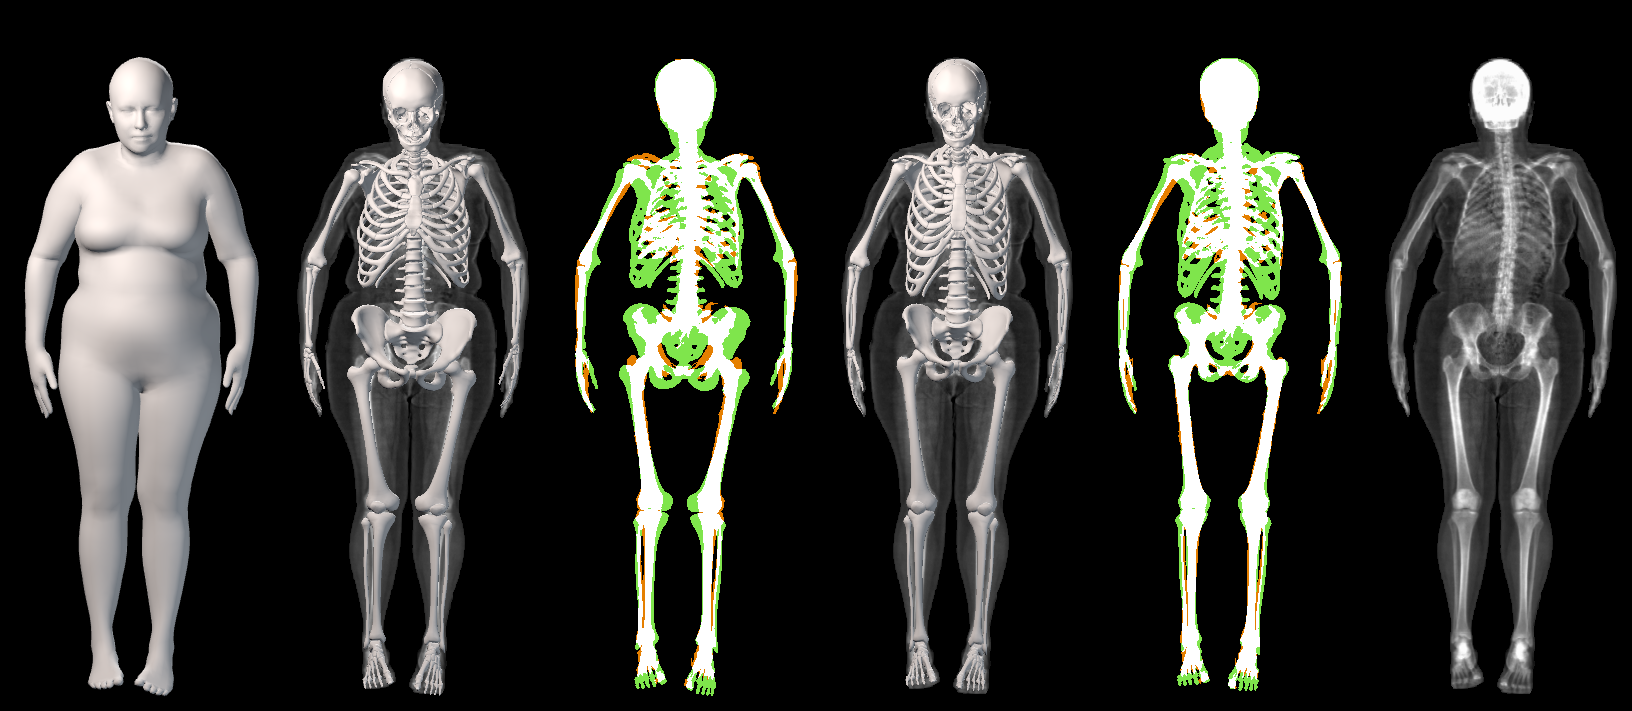

In this work, we address the problem of inferring the human anatomic skeleton, i.e. the bone shapes and locations, solely from surface observations. That is, we infer the bones from the skin. To that end, we learn a statistical model of the skeleton shape and its correlation with the skin surface (Fig. 1 left). Given a posed body, our method predicts the skeleton from the body shape, and poses it inside subject to anatomic constraints (Fig. 1 right).

The presented metric has a limitation: predicting all the skin volume as bone would obtain a perfect result (, ). In Fig. 4 and Sup. Mat. we show that visually, OSSO’s predictions are coherent and match the DXA bone images better than Anatomy Transfer. In Sup. Mat. we provide examples of subjects with high Body Mass Index, for which Anatomy Transfer predicts a stretched skeleton, while ours are closer to the DXA skeleton mask.

5.4 Generalization to new poses

In Figure 19, we present a qualitative comparison between our OSSO predictions and the ones from Anatomy Transfer. This results complement Sec. 5.3 of the main document.

From the DXA test set, we select 5 subjects spanning the dataset BMI distribution. From the skin alignment , we infer the skeleton and compare it to the subject’s skeleton DXA image. We denote the skeleton inferred with AT and the skeleton inferred with OSSO. is the mask rendered from the mesh .

As can be seen from the images, our predictions do better capture the global shape of the skeletons. Particularly, Anatomy Transfer often estimates the location of the hips to be too low with respect to the actual hips location. Our method predicts a skeleton which is visually closer to the one observed in the DXA images.